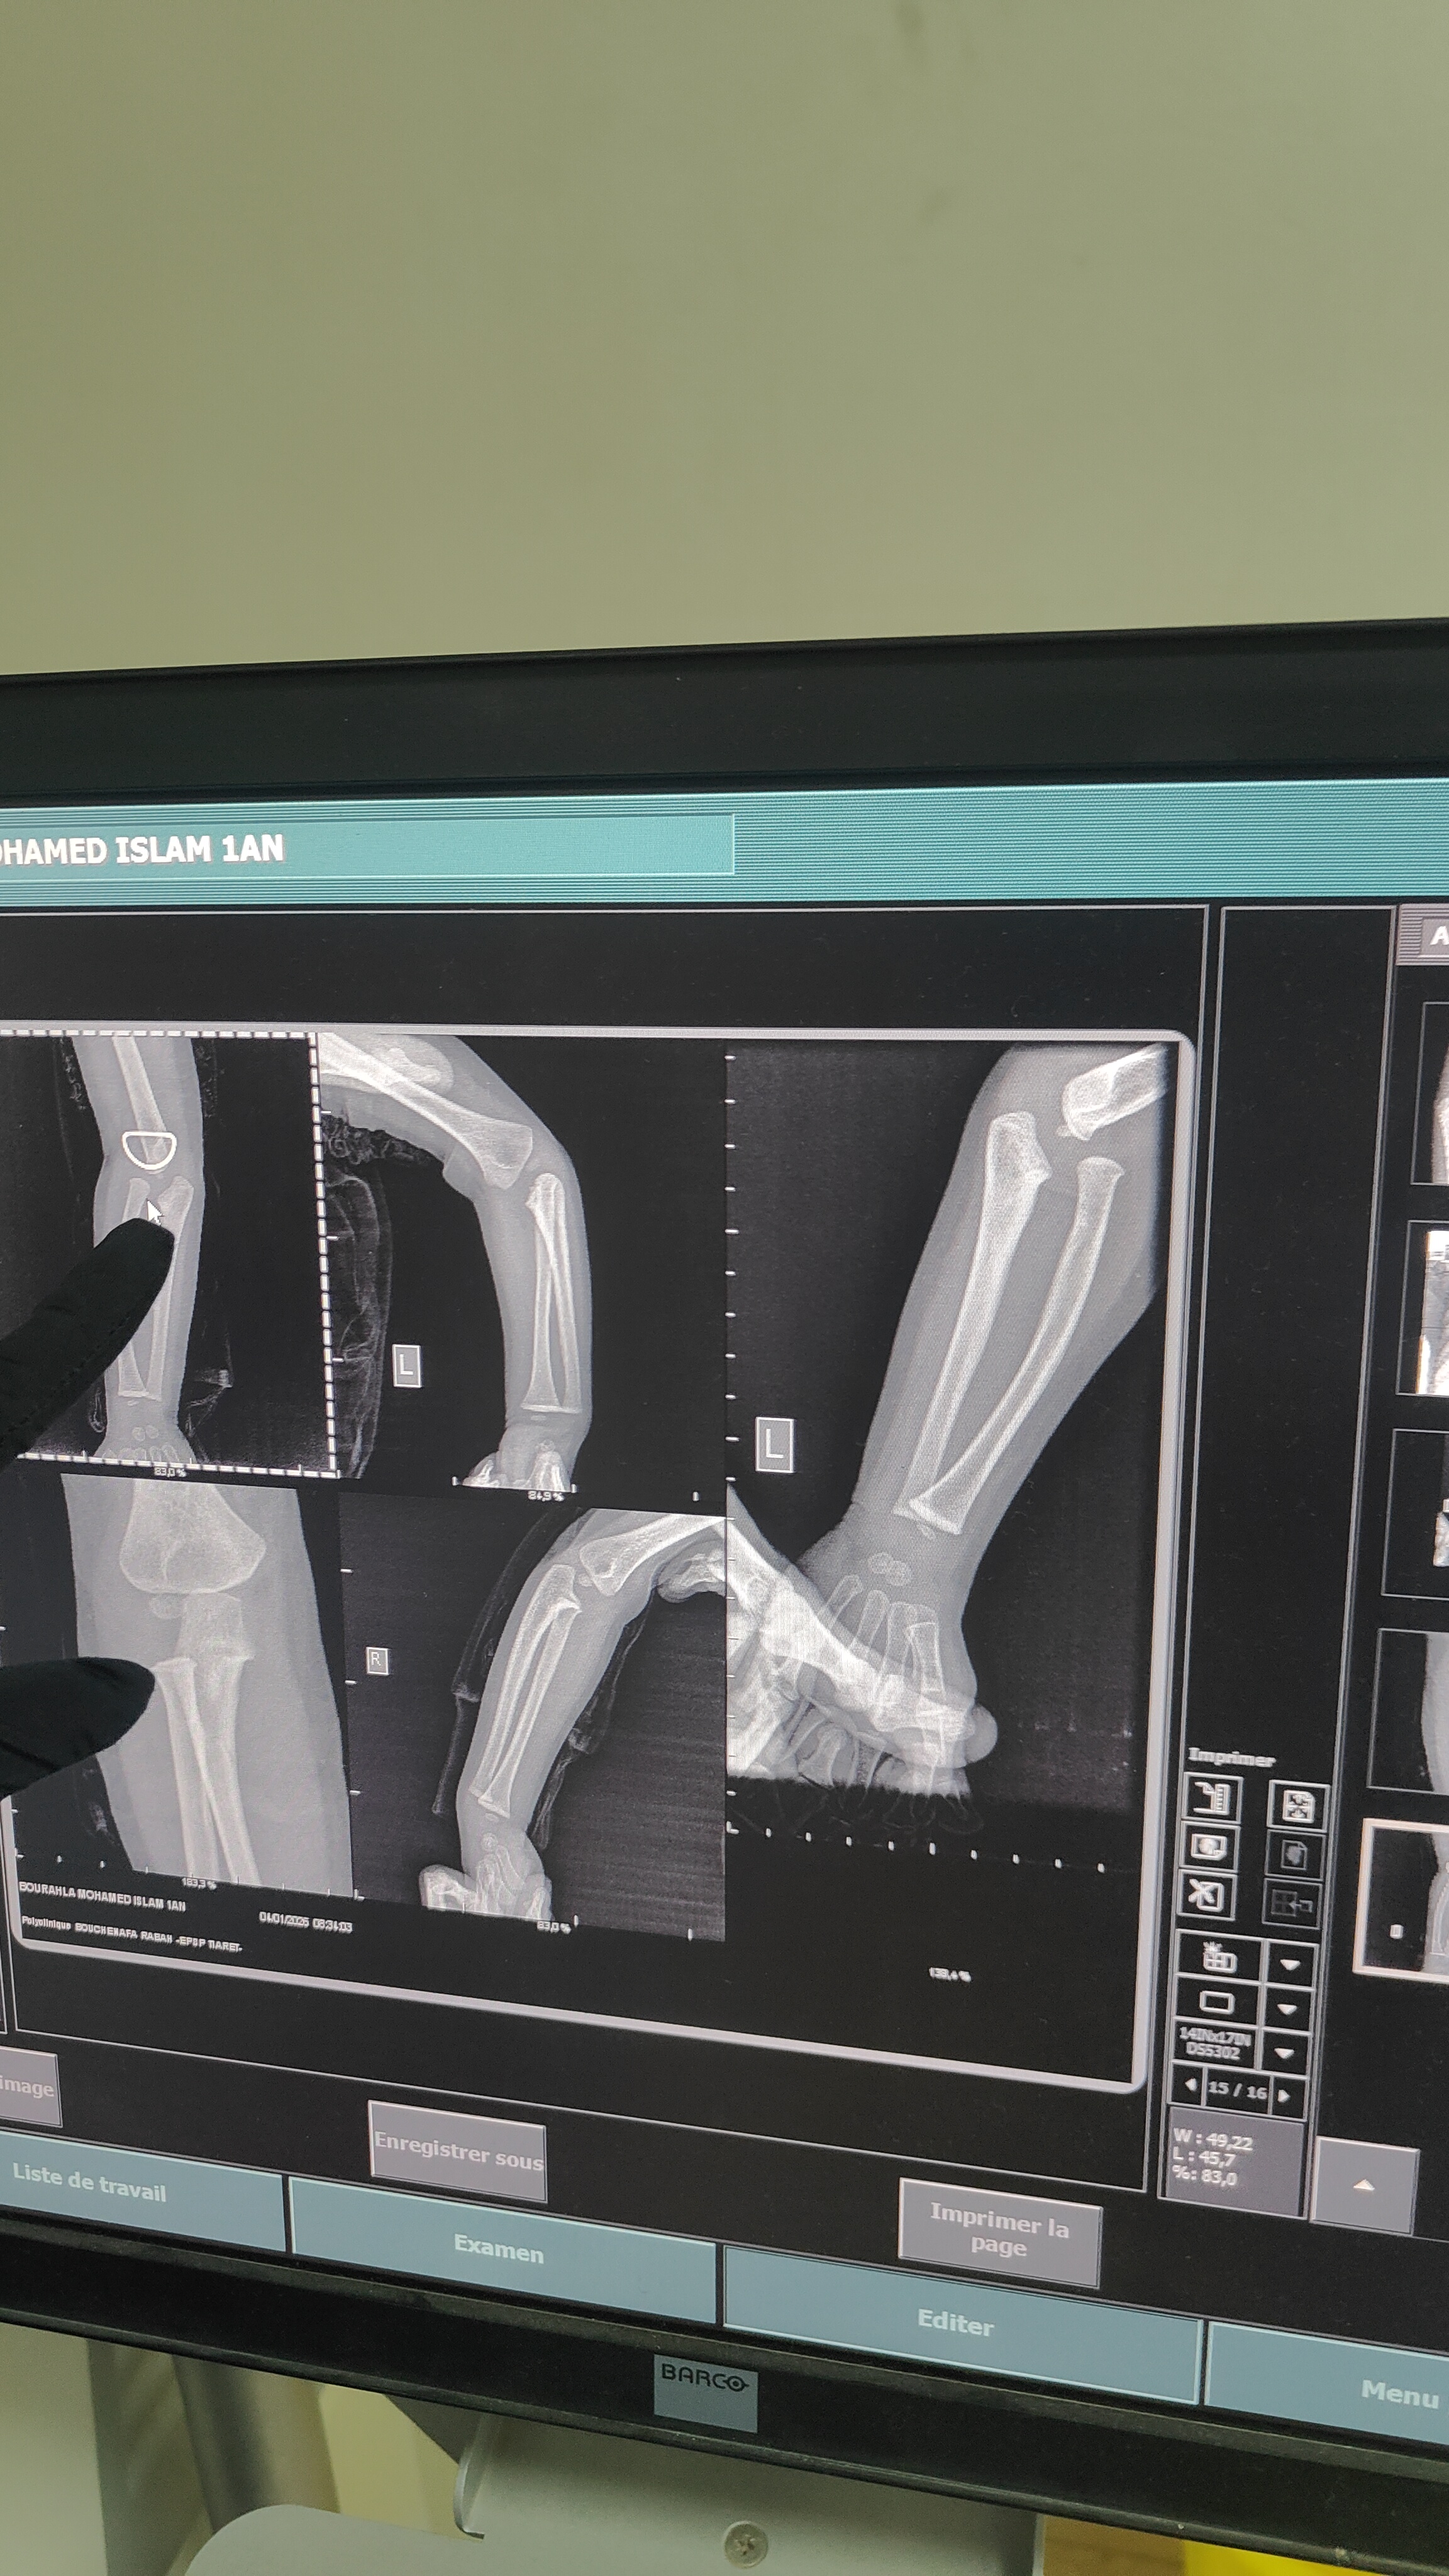

الحالة طفل بسن سنة و6 اشهر منذ الولادة لوحظ انتفاخ في الساعد بالقرب من المرفق ومع مرور الزمن اتضحت صعوبة في دوران اليد يمين يسار ويظهر في اشعة الراديو فراغ عند المرفق يبدو كخلع للعظم